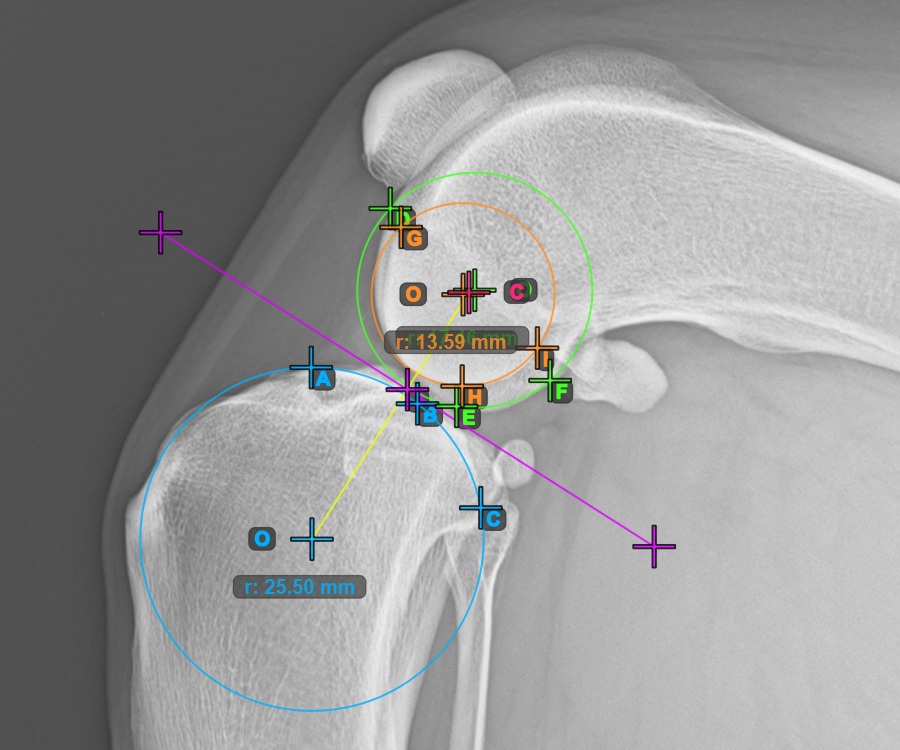

Mark the three points on the main condylus of the tibial bone (Medialis Tibialis). Regardless of the order, make sure to mark the most cranial point, the most caudal point and the midpoint of the Medialis Tibialis. A circle will be automatically constructed based on the three placed points.

The image below represents a typical placement of the three points on the Condylus Medialis Tibialis.